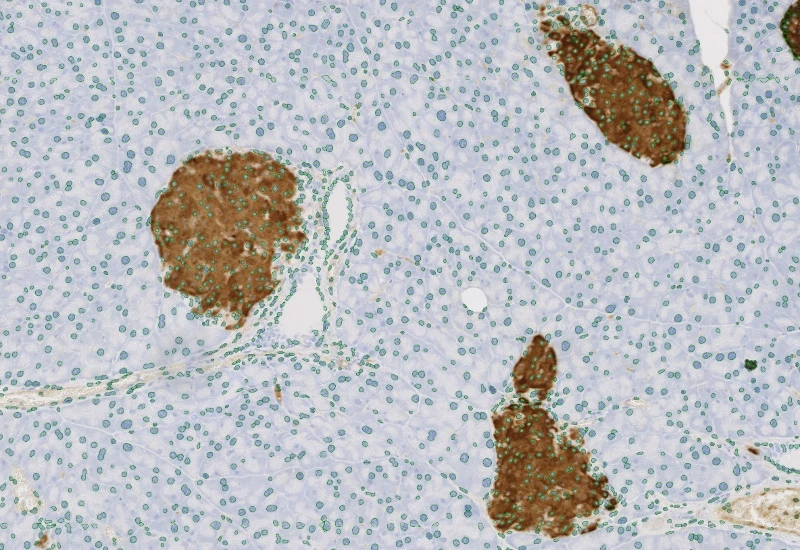

Detect IHC/HC-stained metastructures (e.g. islets, tumor, stroma) and segment single cells into nucleus, perinuclear area, and/or cytoplasm, classify cells inside/outside metastructures, and measure up to 20 intensity, statistic, and morphometric parameters per area and compartment.

insulin islets, pancreas, immunohistochemistry, beta-cells, brightfield

The IHC Meta Cells App combines the detection of IHC/HC stained metastructures (e.g. Langerhans islets, Tumor - Stroma) with single cell detection (segmentation of cells into nucleus, and/or perinuclear area and/or cytoplasm). Detected cells can be classified and visualized as being either within or outside of detected metastructures. Each detected area and cell compartment is measured for up to 20 intensity, statistic and morphometric parameters.

Original image

Nuclei detection

Metastructure detection

Nuclei/metastructure detection